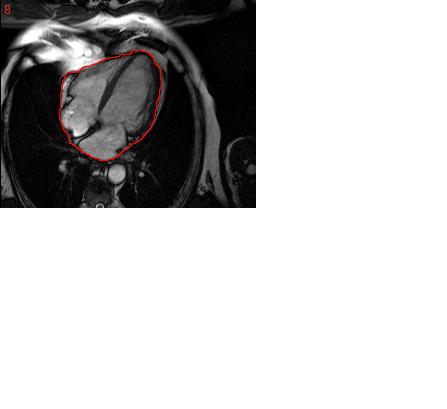

hey, the basic idea is to track the outer walls of the heart (the out line in red)

this video might give you a bettr idea

now as you can see this shows from a lot of views now we are more concerned with following the outer muscle of any one particular sequence.

i will leave the exact sequence for you too choose(any one sequence will do).